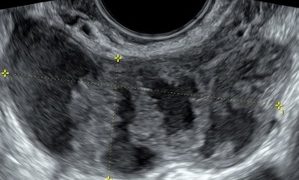

Leggi di piùCari soci, questo mese un nuovo "How to do", sulla conta dei follicoli antrali. Per un problema tecnico non è stato possibile integrare l'audio, ma trovate in basso la versione...